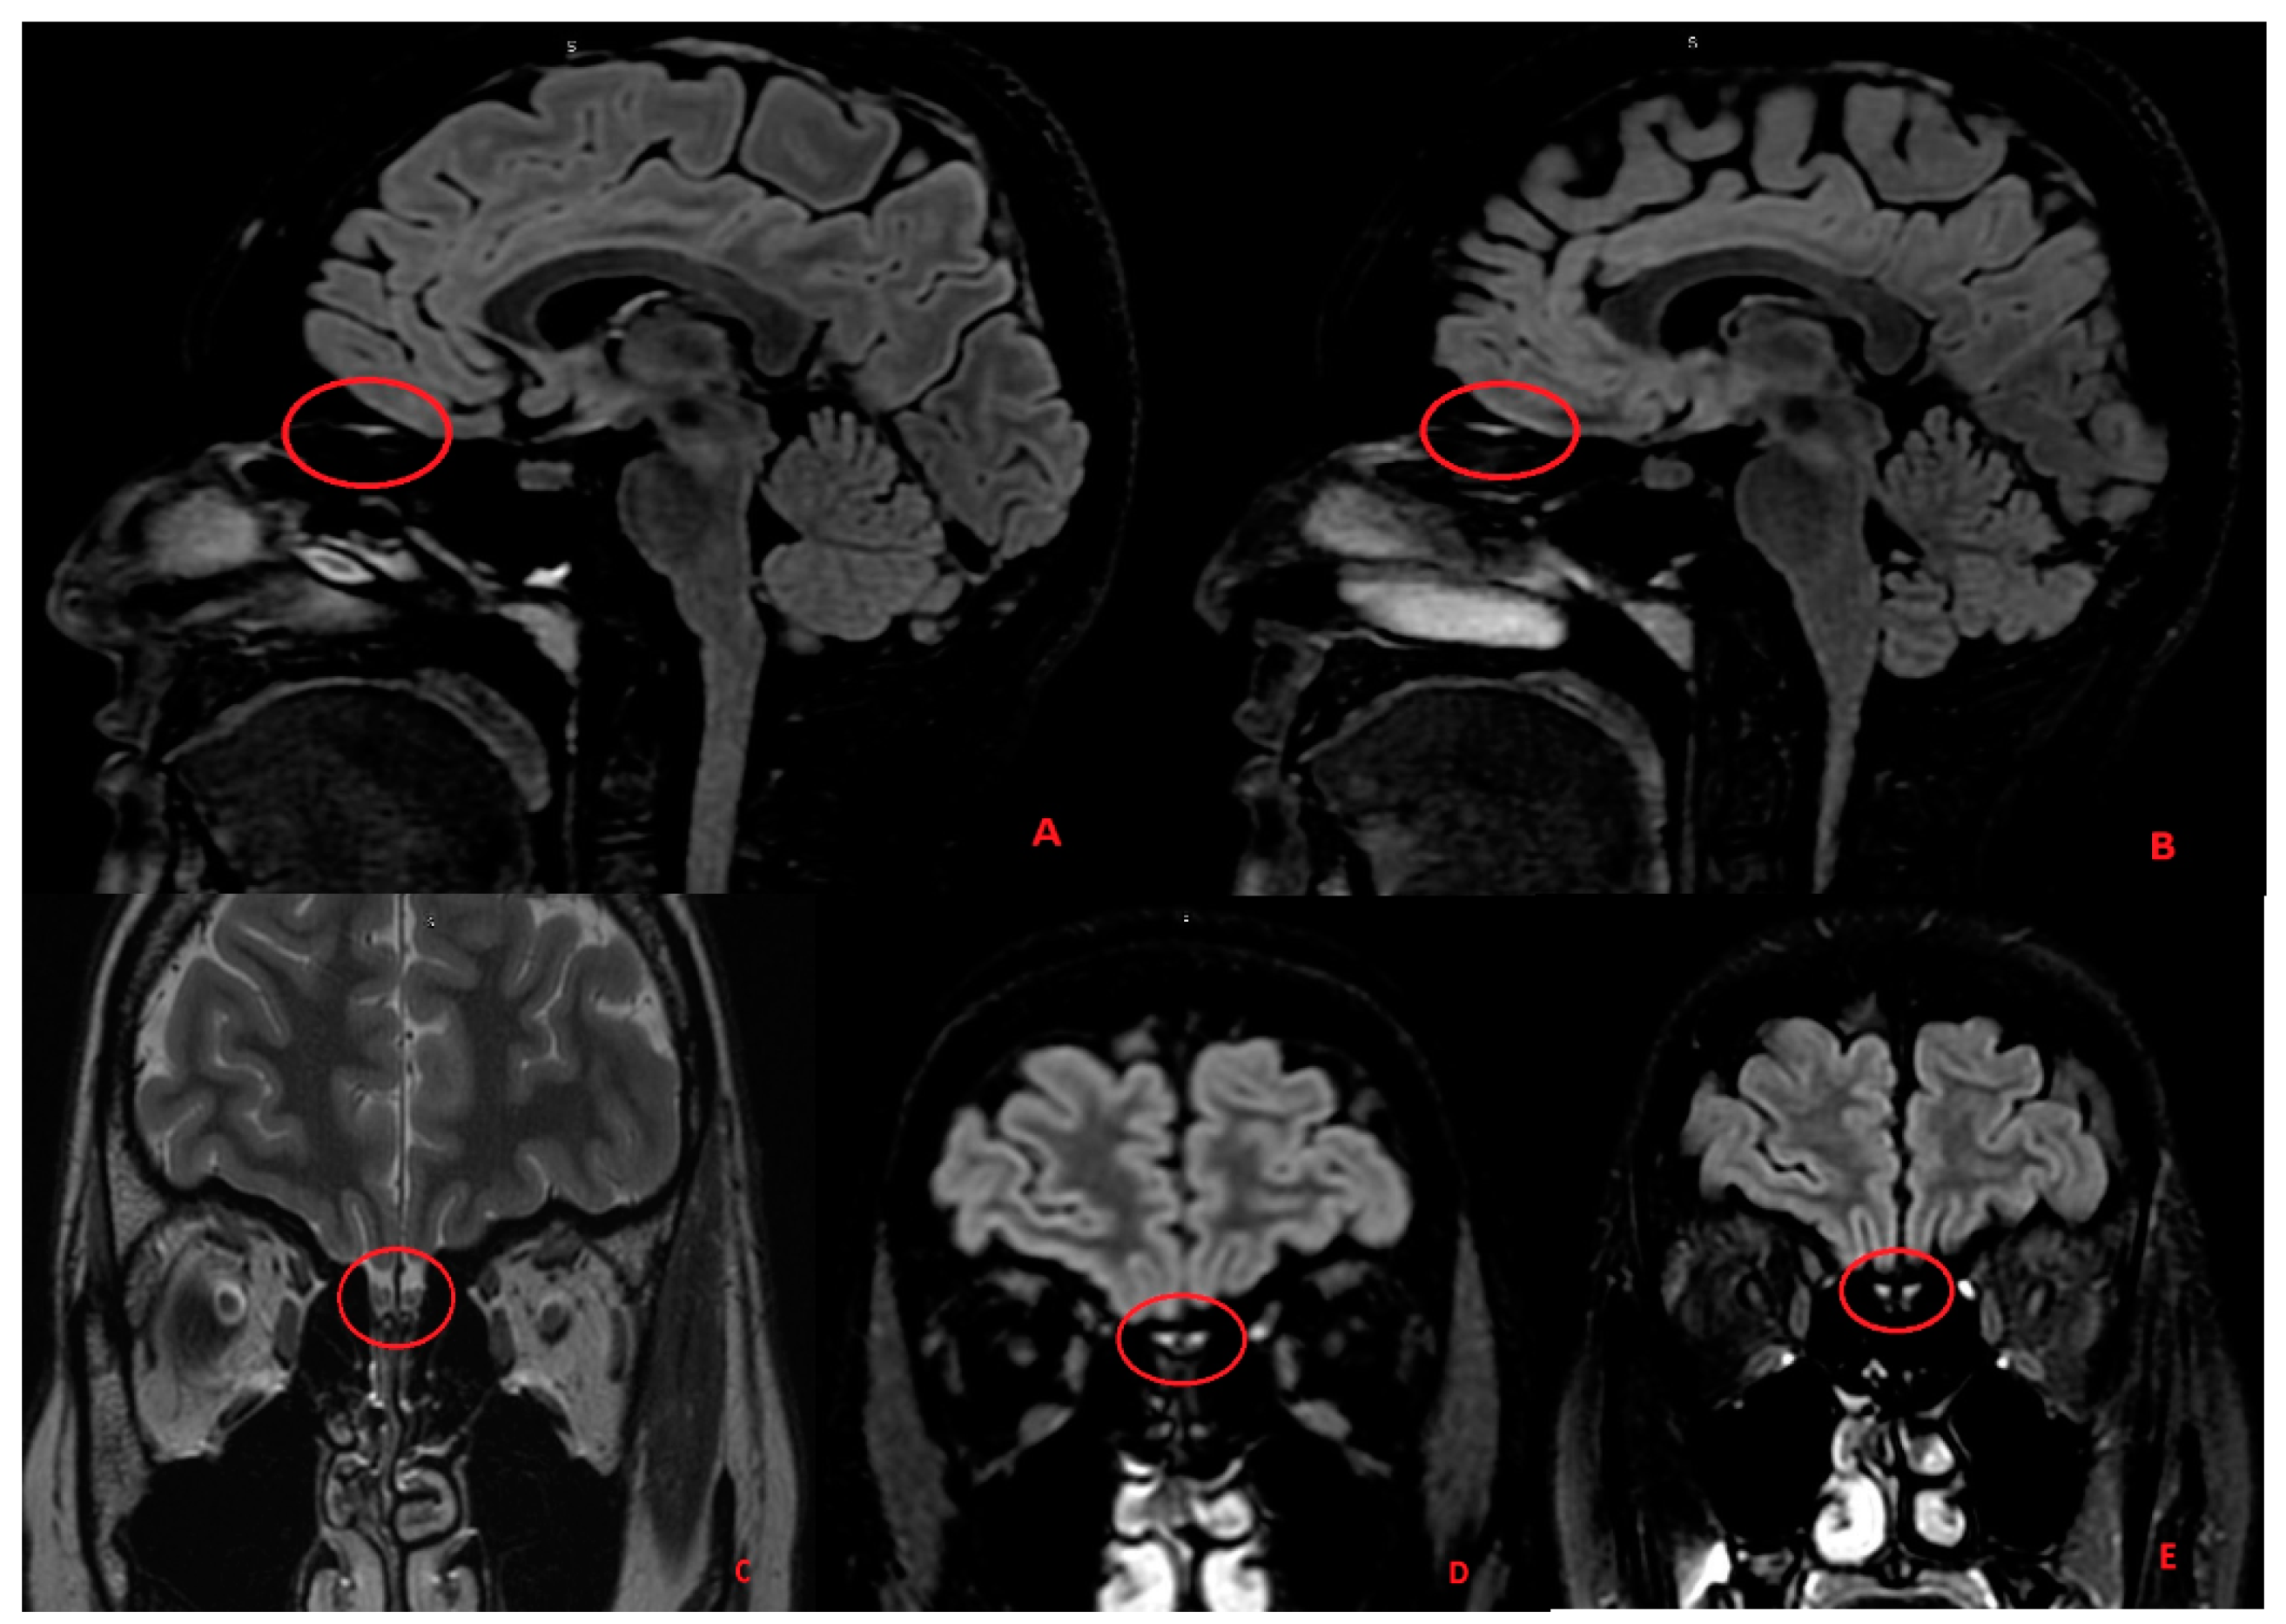

3. Case Report 1

3.1. Discussion Part I—Neuro-Invasion Mechanism: Can SARS-CoV-2 Directly Invade the CNS?